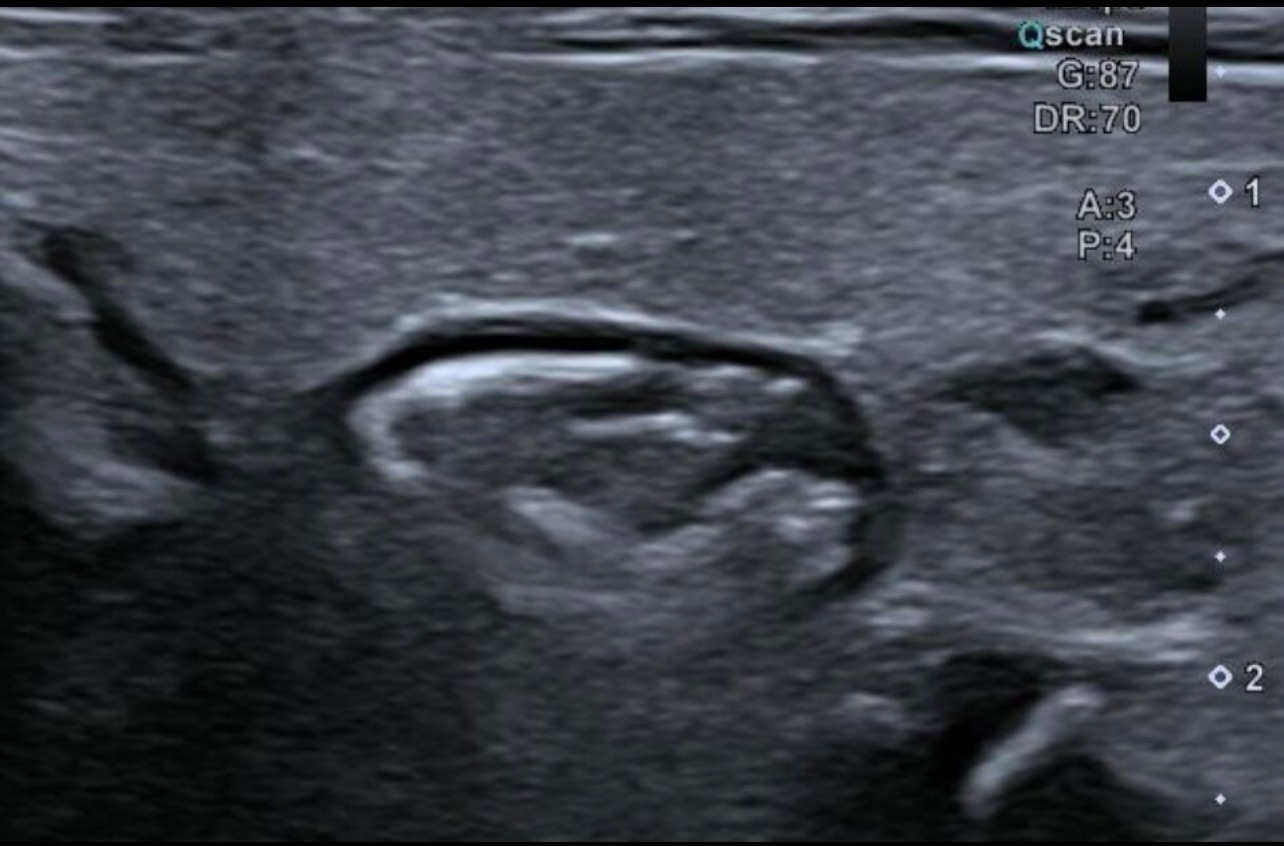

• Il s'agit d'un "nodule" situé à la partie postérieure du lobe gauche.

• Aspect particulier avec un piqueté échogène et des limites floues sur le versant médial et au contraire nettes en antérieur et latéral.

• Les manœuvres de déglutition permettent de montrer que de l'air se glisse dans la masse et qu'il existe un raccordement à l'œsophage.

Ce n'est donc pas un nodule Thyroïdien mais un véritable diverticule de Zenker.